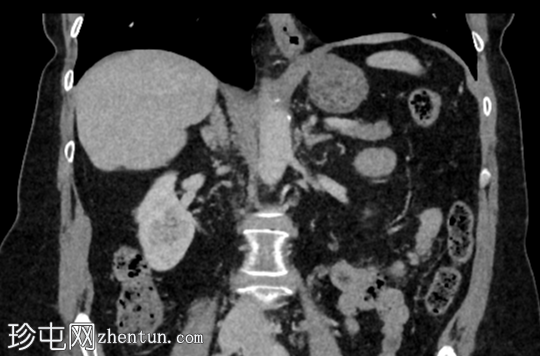

冠状位增强扫描(门静脉期)

3.png

右肾后上极可见2.8 cm外生性强化病灶,提示肾细胞癌(RCC)。右肾静脉和下腔静脉通畅。未见明显局部淋巴结肿大。右肝叶可见高密度金属影。可见含脂肪的脐疝。